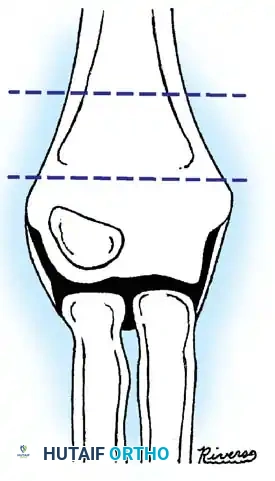

Fig. 33-40 Examples of angulation, translocation, and total displacement of radial neck fractures.